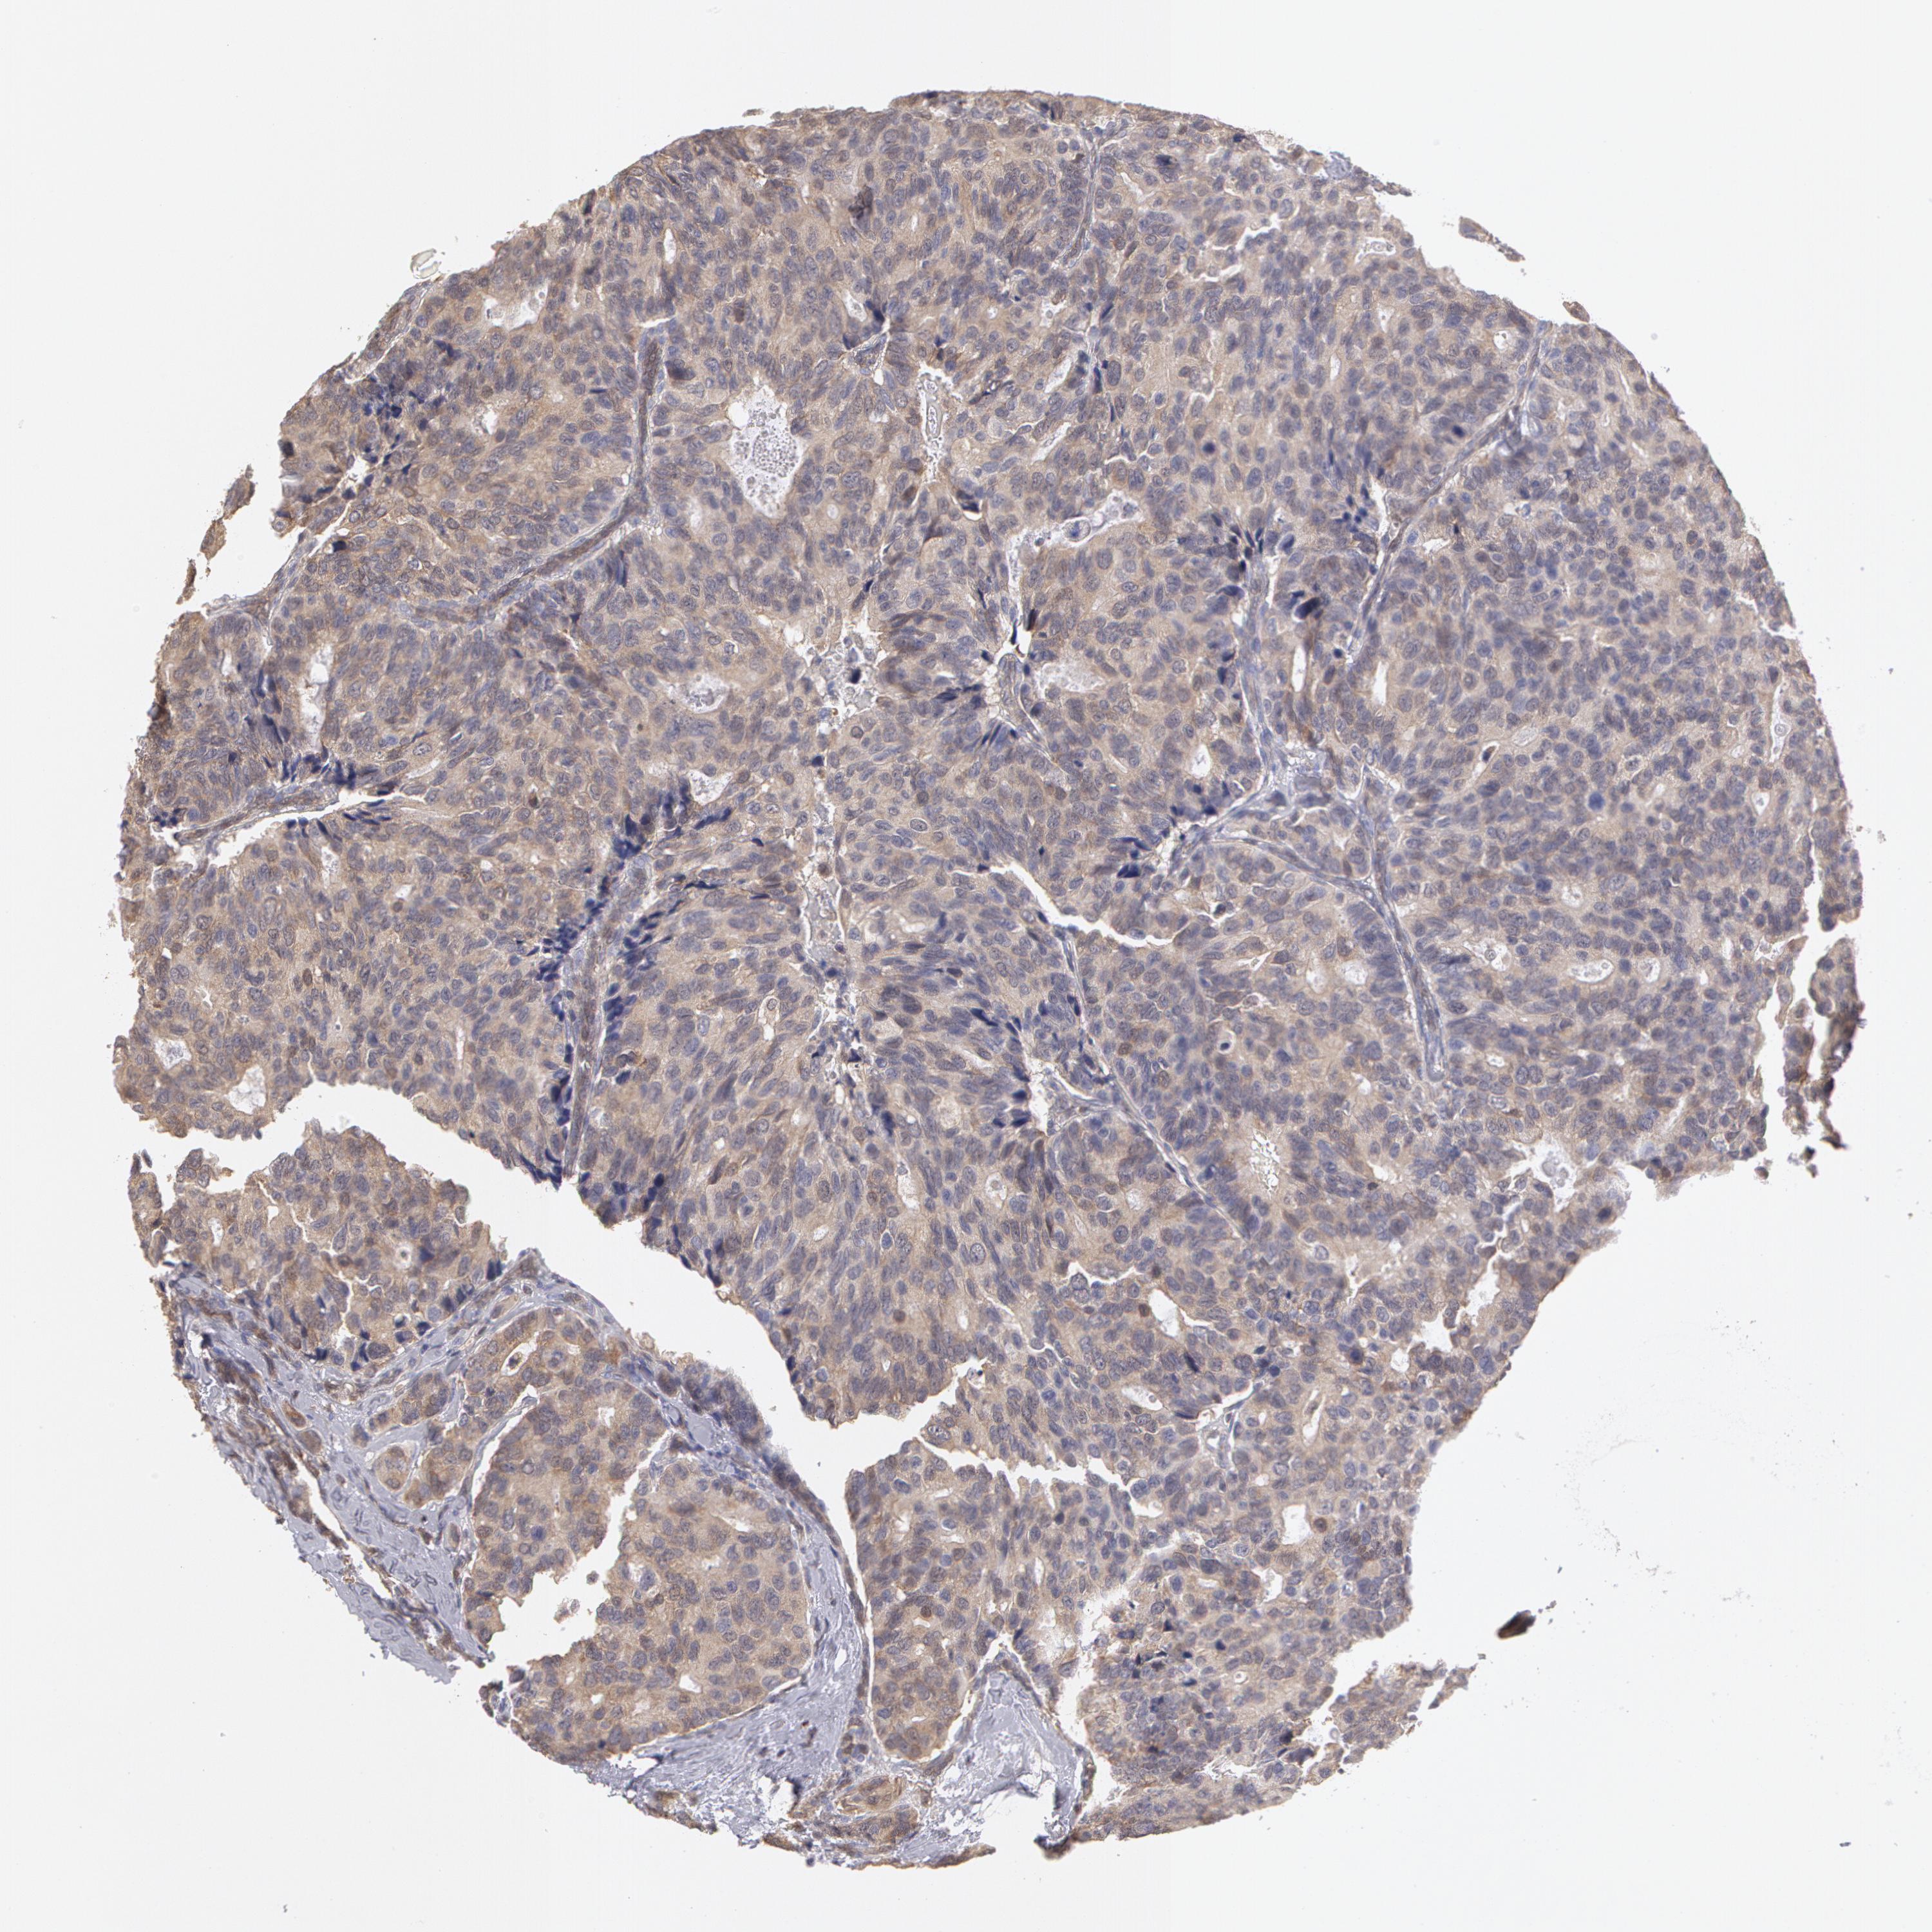

CANCER BREAST CANCER Show tissue menu

BRCA TCGA BRCA VALIDATION PROTEIN EXPRESSION

Breast cancer

Human cancer